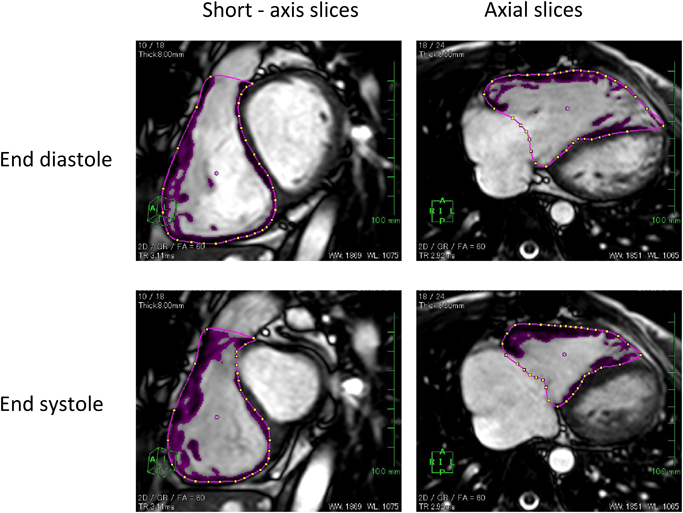

CMRでは心室全体が乳頭筋を含めて明瞭に描出されることで,ありのままの左右心室の姿(容積・拍出量・心筋重量・壁運動)が数値として表現される.撮影方法は一貫しており,検者によって評価断面がずれる心エコーと比較して再現性という点でも有利である.心室容積計測(解析)は一般にSimpson法(ディスク法)で行われる.左右心室ともに撮影できる短軸像(SA: Short-Axis)から求めるのが一般的で,各時相の心内外膜面をトレースすることで算出される(Fig. 1左).Mooijら23)は,60小児例のCMRから,右室拡張末期容積・心筋重量の検者内および検者間変動係数は6.4%および11.3%と低く,左室の3.6%から10.5%と変わらないと報告した.Grothuesら24)は,同係数を6.2%と8.7%と報告している.Clarkeら25)は,CHD50例でSA planeとaxial planeを比較し,右室収縮末期容積以外,両者に有意差なしと結論した.Blalockら26)は,ファロー四徴症(TOF)30例の右室容積・心筋重量・EF等が,同一症例の時期の異なる検査間でも高率に一致することを示し,経時的変化をとらえることができると主張した.

一方で,計測(解析)方法が適切でなければ,当然その値は不正確となる.誤差を生む最大の要因は,心基部(心房心室境界)および乳頭筋のトレース法にある.左右心室とくに右室では心基部の正確な同定には経験が必要である.基部を明瞭に判別するために,Axial planeでの撮影から容積計量する方法も推奨される(Fig. 1右).また,乳頭筋を一切無視する(内腔に含める)と左室については容積が6.5%増大するとされる27).特に心肥大の強い右室ではその影響が大きく,誤差が増大するため,pixel-intensityから乳頭筋を自動的に判別し内腔から除外できるソフトの使用が勧められている28)Fig. 2は自験例の心室容積をCMRとAngiogramで比較した図である.良好な相関が得られており,今まで用いてきた心カテによる心室容積と同様の臨床感覚で,より正確なCMRによる心室容積を用いることができる.

Fig. 1 Sample images of endocardial contours